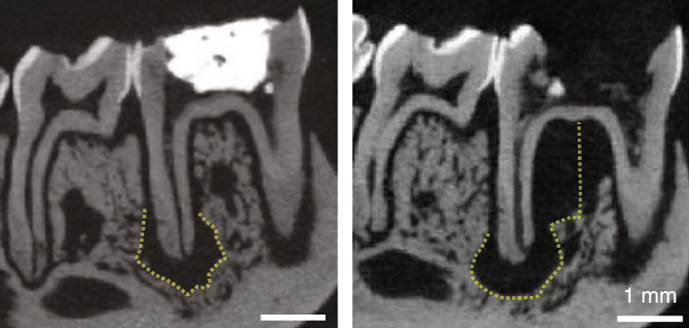

root canal scans

CT scans show that an animal tooth treated with lab-made HDL during root canal treatment (left) had less bone loss (black region outlined by yellow dashes) compared to a tooth that did not receive the treatment (right). | Bottino Laboratory

Finally, the team tested the ability of lab-made HDL to improve root canal treatments in rats by comparing it to the standard treatment using bleach and calcium hydroxide. They found that lab-made HDL treatment was comparable to the standard therapy in reducing bone loss. Additionally, teeth treated with bleach and lab-made HDL had fewer pro-inflammatory immune cells in the root tissue than those treated with bleach and calcium hydroxide, indicating less inflammation in the lab-made HDL-treated teeth.